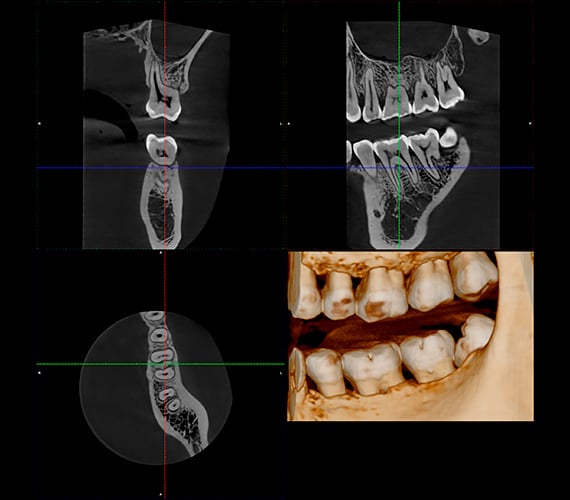

Imágenes de última generación, ahora al mejor precio. Consigue tu equipo 3D Planmeca Viso con una promoción única.

Planmeca Viso G1 con condiciones únicas de financiación y soporte.